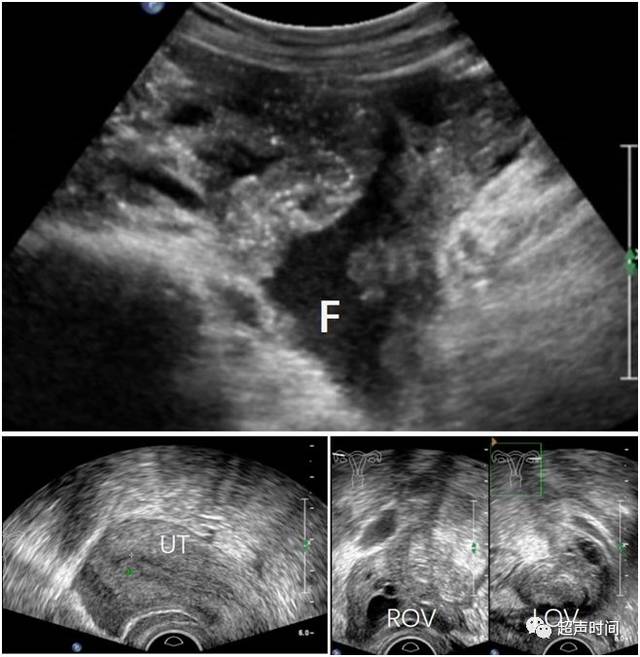

上腹部疼痛,但超声只发现盆腔积液,怎么考虑?

推荐回答 病情分析: 你好,从超声报告看陶氏腔积液就是盆腔积液

陶氏腔可见范围约35×16mm的无回声暗区是什么意思?